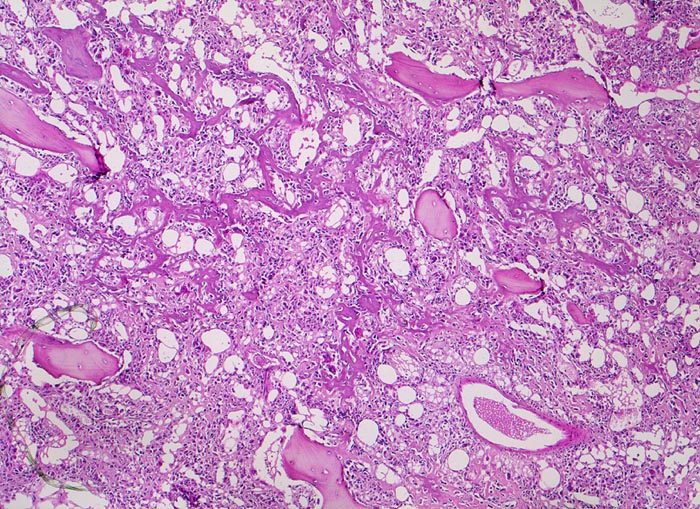

PathoPic – image database / PathoPic ID 4790 - Osteosarkom

Osteosarkom

Knochen, Femur

Die breiten ursprünglichen lamellären Knochenbälkchen sind weitgehend erhalten. Das von den atypischen Tumorzellen gebildete unregelmässige und fein vernetzte Tumorosteoid liegt in den Markräumen und lagert sich teilweise dem ortsständigen Knochen an.

16 jähriger Jugendlicher mit seit mehreren Wochen bestehenden belastungsunabhängigen Schmerzen im distalen Femur rechts oberhalb des Knies (Metaphyse). Im Röntgenbild irreguläre Verdichtung, zum Teil auch Aufhellung der ursprünglichen Knochenstruktur mit Zerstörung der Corticalis und spiculaartige (=sonnenstrahlenähnliche) Periostreaktion. Im Serum erhöhte alkalische Phosphatase.

Histologie

50